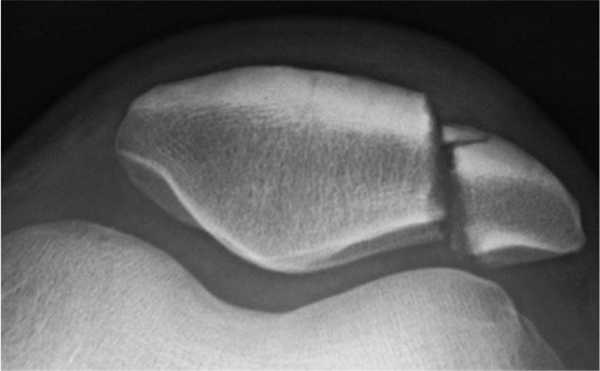

Перелом надколенника (коленной чашечки) на КТ

МСКТ коленного сустава (коронарная проекция)